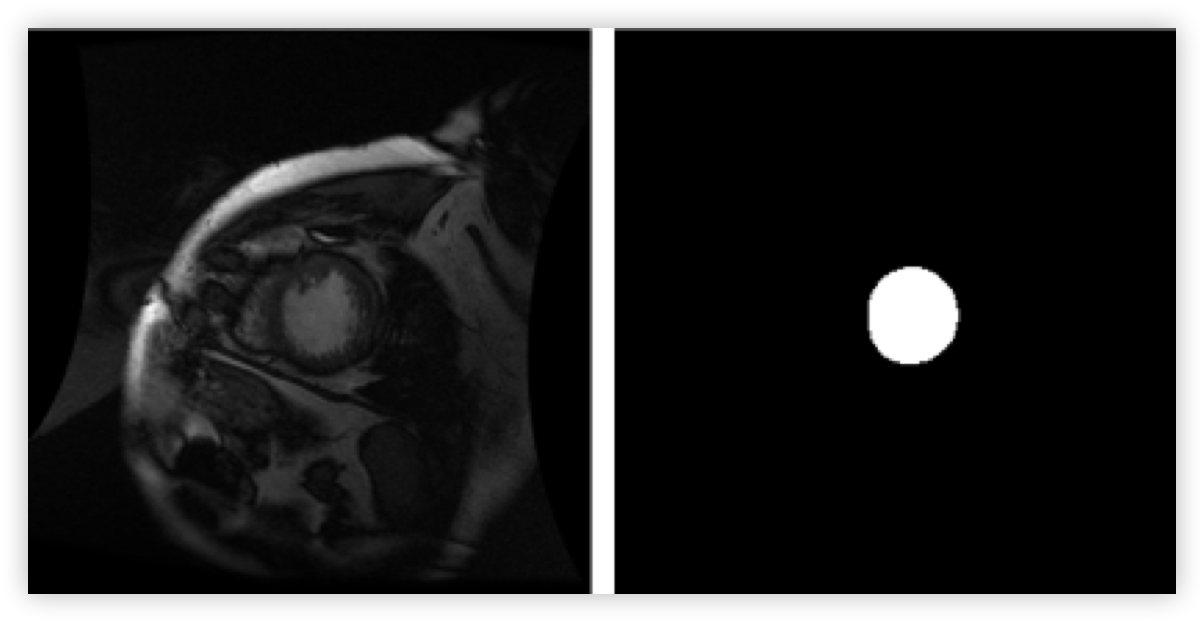

In this tutorial we will see how DLP may be used to train a semantic segmentation network for medical imaging. More specifically, we will use the Sunnybrook Left Ventricle Segmentation Challenge Dataset to train a Caffe model to segment the left ventricle out of MRI images. By the end of this tutorial, you will be able to take a single MRI image, such as the one on the left, and produce a labelled output - outlining the location of the left ventricle in the MRI input image - such as the image in the right.

In this tutorial, we will use the Sunnybrook Left Ventricle Segmentation Challenge Dataset. The dataset consists of 16-bit MRI images in DICOM format and expert-drawn contours in text format (coordinates of contour polylines). A sample image/label pair may look like:

Now all what remains to do is to load an image like the one on the left, and the model will output the same image but with the predicted location of the left ventricle highlighted like the image in the right.